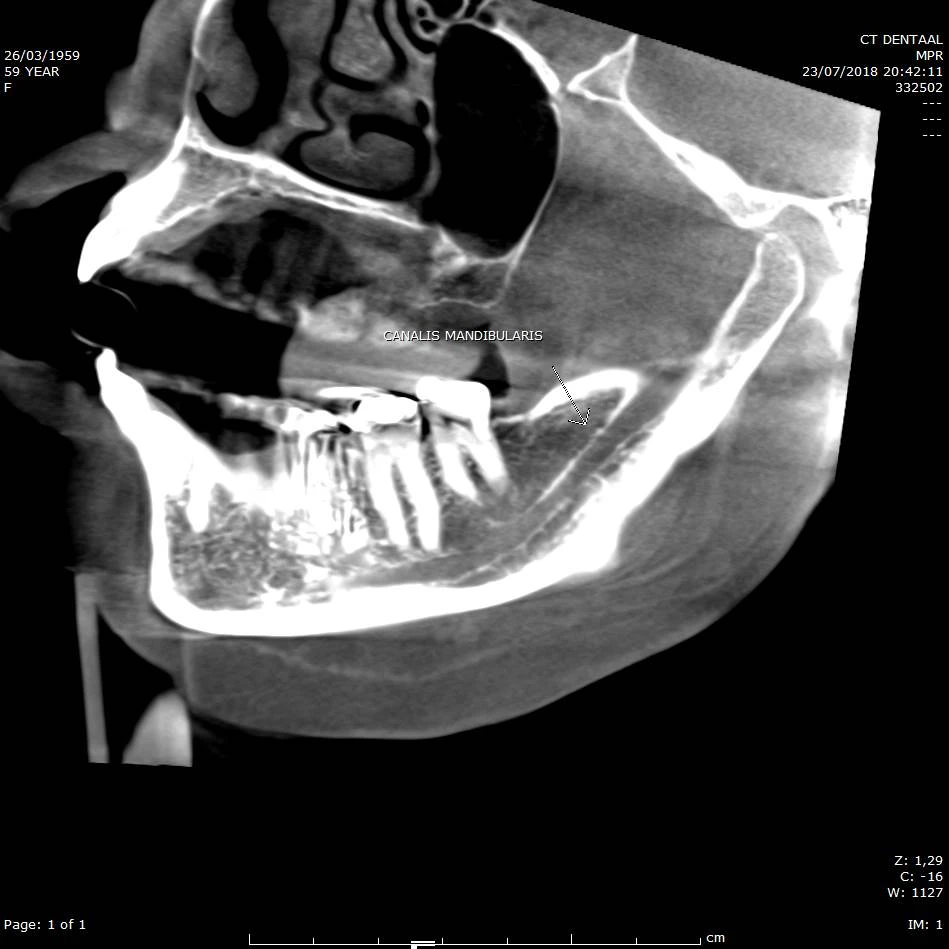

Bepaling bothoogte/breedte voor implant planning. Ligging van de nervus alveolaris inferior (n. mandibularis).

CBCT voorbeeld 8: canalis mandibularis sagittaal

Sagittale doorsnede: visualisatie van de canalis mandibularis